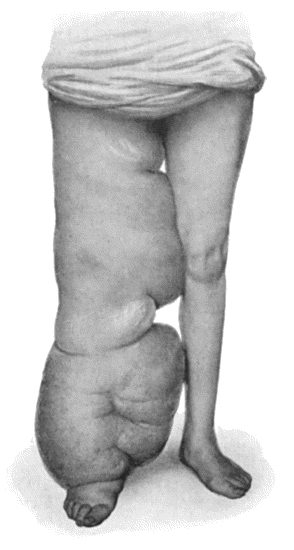

89.Elephantiasis Neuromatosa in a woman æt. 28 359

97.Elephantiasis in a woman æt. 45 387

98.Elephantiasis of Penis and Scrotum 388